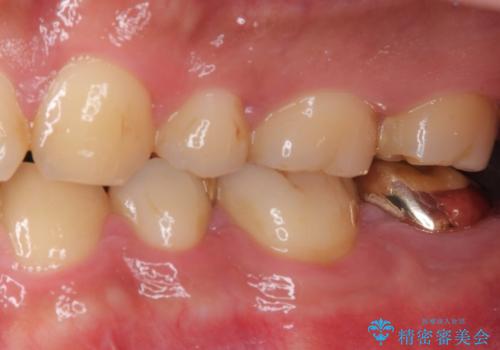

上顎の歯をアンカースクリューを用いた部分矯正により位置を修正し、根管治療後にPGAクラウンにて補綴治療を行うこととしました。

歯列が整ったことで咬み合わせが非常に安定しました。